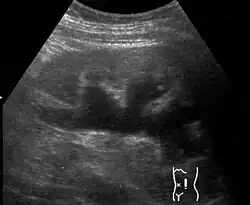

Renal ultrasonography of hydronephrosis[16]

| Renal ultrasonography of hydronephrosis caused by a left ureteral stone | |